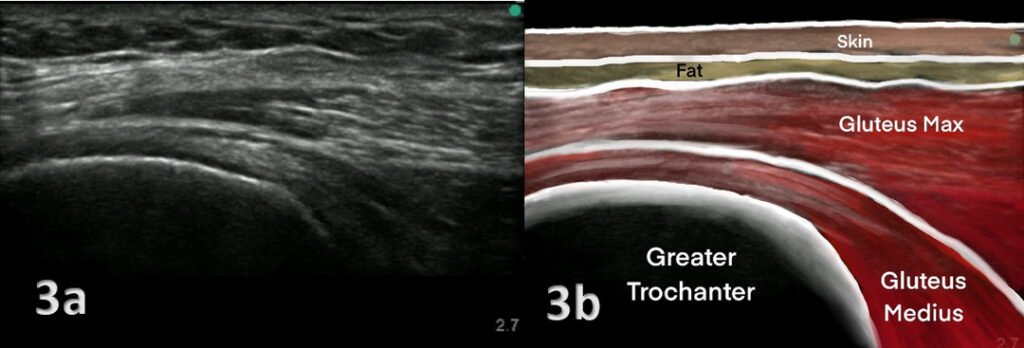

- X-Rays: X-rays can help rule out other causes of hip pain, such as fractures or arthritis.

- MRI (Magnetic Resonance Imaging): An MRI provides detailed images of the soft tissues, tendons, and bursae. It can reveal inflammation, tendon tears, or degeneration.

- Ultrasound: An ultrasound scan can be used to detect bursitis or damage to the gluteal tendons.